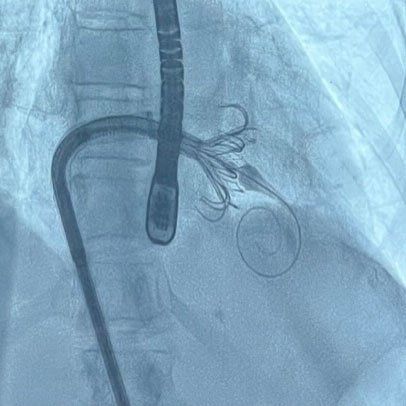

A tricuspid device is implanted on the heart with a catheter.

A tricuspid valve is implanted in the heart via catheter.

The EVOQUE tricuspid valve replacement system is an investigational device designed to replace native tricuspid valve without open-heart surgery. The valve is implanted using a minimally invasive delivery system (catheter) through the femoral vein reaching to the heart.